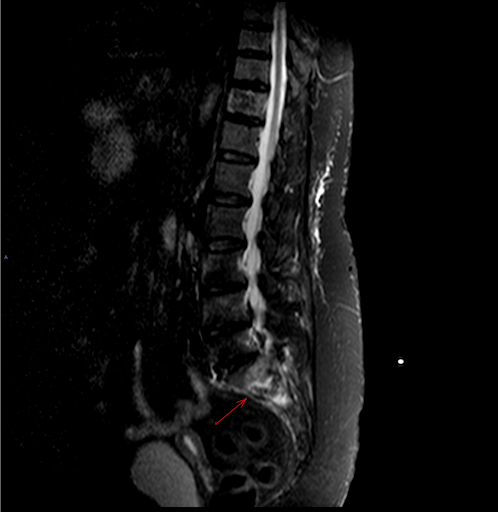

Figura 4: RMN arătând fractură de insuficiență sacrală pe fond de osteoporoză și paratiroidectomie

the msk playbook spinal insufficiency fractures

Figura 5: RMN arătând fractură de insuficiență sacrală pe fond de osteoporoză și paratiroidectomie

Figura 6: RMN arătând fractură de insuficiență sacrală pe fond de osteoporoză și paratiroidectomie